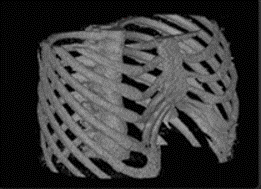

在应用案例中,经过对应用该算法的深度学习Caffe框架的数据训练,其成功实现了从胸部CT影像中自动化识别和提取胸骨组织。同时,在对被识别和提取的骨组织影像进行排序和整理的此基础上,该研究优化了体绘制算法并利用OpenGL渲染技术实现了胸骨组织的几何自动化建模。

从而,算法和程序实现了从胸部CT影像的导入直到相关骨组织的识别、提取和几何重构建模的所有工作自动化完成。基于人工智能深度学习的高识别精度,上述所有识别和建模工作均可一次性精准地自动化完成,无需额外的人工修正。